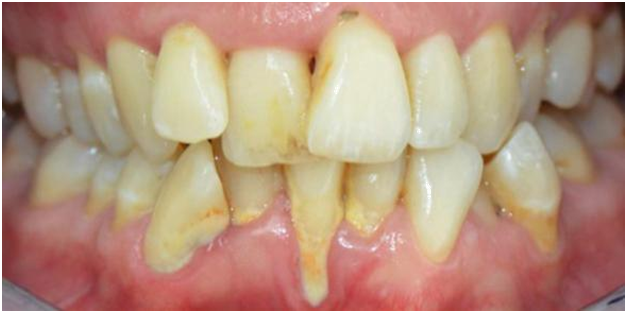

The second case (Figure 3) displays moderately malpositioned mandibular anterior teeth and essentially illustrates the method and apparatus for the restoration of alveolar bone morphology. The patient presented to a FASTBRACES® provider's private practice with a chief complaint of unfavorable esthetic appearance as it relates to moderate alveolar bone hypoplasia or Orthodontosis™ labial to the lingually displaced mandibular incisors roots. This results in a deficiency of alveolar bone labial to the central incisor that demonstrates the gingival recession. The treatment objectives, in this case, are to restore the morphology of alveolar bone around the malpositioned teeth which in turn will allow for new bone to cover the recession.

The patient received scaling and root planing followed by the application of brackets on the four maxillary anterior teeth for patient comfort (Figures 4). A subsequent appointment specifically addresses the application of brackets on the lingually inclined teeth while avoiding bracket application on labially inclined teeth (Figure 5). As the roots of previously lingually inclined teeth upright, brackets are placed on all teeth at a subsequent appointment (Figure 6). Clinical results along with photographs comparing pre and post treatment show dramatic periodontal and esthetic improvement, particularly with alveolar bone development and the reversal of recession (Figure 7). Treatment results are impressive as uprighting of the malpositioned roots creates remodeling of alveolar bone to accommodate the boney support of the properly aligned tooth. Post-treatment results also show a stable occlusion with proper overjet and overbite relations.

The third case highlights the method and apparatus for the treatment of Orthodontitis ™ and showcases treatment progress of uprighting the mandibular left lateral incisor. Note the straightening of the wire reflects and corroborates the uprighting root movement, the appearance of healthy soft tissue and the elimination of cleft formation previously associated with Orthodontosis™

The successful completion of this case highlights the clinical benefits of orthodontic intervention including improved alveolar bone architecture with the reversal of gingival recession, proper root alignment, improved function, and improved esthetics. This case also showcases the capabilities of FASTBRACES ® Technologies as a safe, effective and complete treatment non-extraction both for the periodontally compromised patient and among a diverse set of clinical presentations (Figure 8).23−28